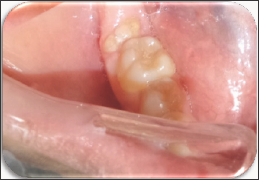

The case of erupted complex odontoma in mandibula was reported in this paper. The clinical and radiological examinations of a 12-year-old girl referred to the pediatric dentistry clinic with complaints of pain in the right mandibular region were performed. In the anamnesis taken from the patient, it was learned that she had no systemic disease. During her intraoral examination, a tooth-like tissue was observed inside of the gingiva in the right mandibular posterior region (Figure 1). No inflammation or ulceration was found in the mouth. During radiographic examination, it was observed that the patient's tooth number 47 was congenitally missing (Figure 2). The pre-diagnosis of complex odontoma was made after the clinical and radiological examinations. The patient was taken under an operation under local anesthesia and was operated with surgical procedures. As a result of the histopathological examination of the biopsy material obtained, the complex odontoma in opaque color with a dimension of 0.8x0.7x0.7 cm was confirmed (Figures 3-4).

Figure 1: Intraoral Appearance.